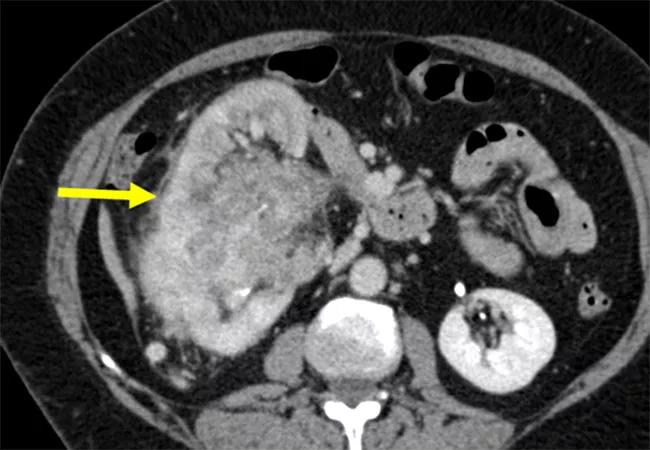

Most renal masses are solid and well-defined. A minority are infiltrative renal masses (IRMs) which have a poorly defined interface with the normal parenchyma and markedly irregular shape. It is well established that IRMs are mostly malignant and aggressive. The differential diagnosis includes poorly differentiated renal cell carcinoma (RCC), urothelial carcinoma (UC), lymphoma, metastatic cancer and sometimes inflammatory or infectious causes.

Based on a blinded, independent review by two radiologists, 133 IRMs were identified in the cohort. They represent 25% of all patients with locally advanced stage and/or aggressive histology, a higher incidence compared with most other studies in the literature. Of that number, 109 IRMs were imaged at Cleveland Clinic and could be evaluated regarding documentation of infiltrative features. Only 42 (39%) were documented as IRMs within the radiology reports and only four by the surgical team. The IRMs that were documented tended to be extensively infiltrative and those that were undocumented were more likely to be focal.

Compared with non-IRMs, the IRMs had significantly larger tumor size and increased tumor complexity. On final pathology, 103 IRMs (77%) were diagnosed as RCC and 59 (57%) had sarcomatoid/rhabdoid or other poorly differentiated features. Undocumented IRMs were significantly larger than documented IRMs, which is likely due to the lower percentage of UC cases in the undocumented cohort.

Regarding outcomes, the two-year cancer-related mortality (CSM) was 29% for IRM patients and 6% for non-IRM patients; poor prognosis was observed in both documented and undocumented IRMs. “This study shows that IRMs have a markedly worse prognosis than non-IRMs. It is significant that the IRMs had much more unfavorable outcomes than the non-infiltrative masses, which also had aggressive pathologic characteristics. They are also more common than we realized,” says Steven C. Campbell, MD, PhD, urologic surgeon and a member of the Section of Urologic Oncology in Cleveland Clinic’s Glickman Urological and Kidney Institute.